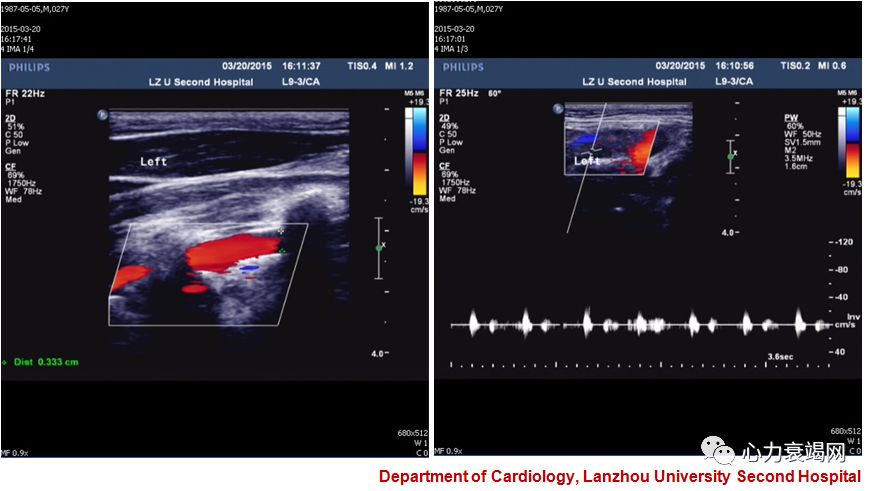

1.应激性心肌病 左室心尖部血栓